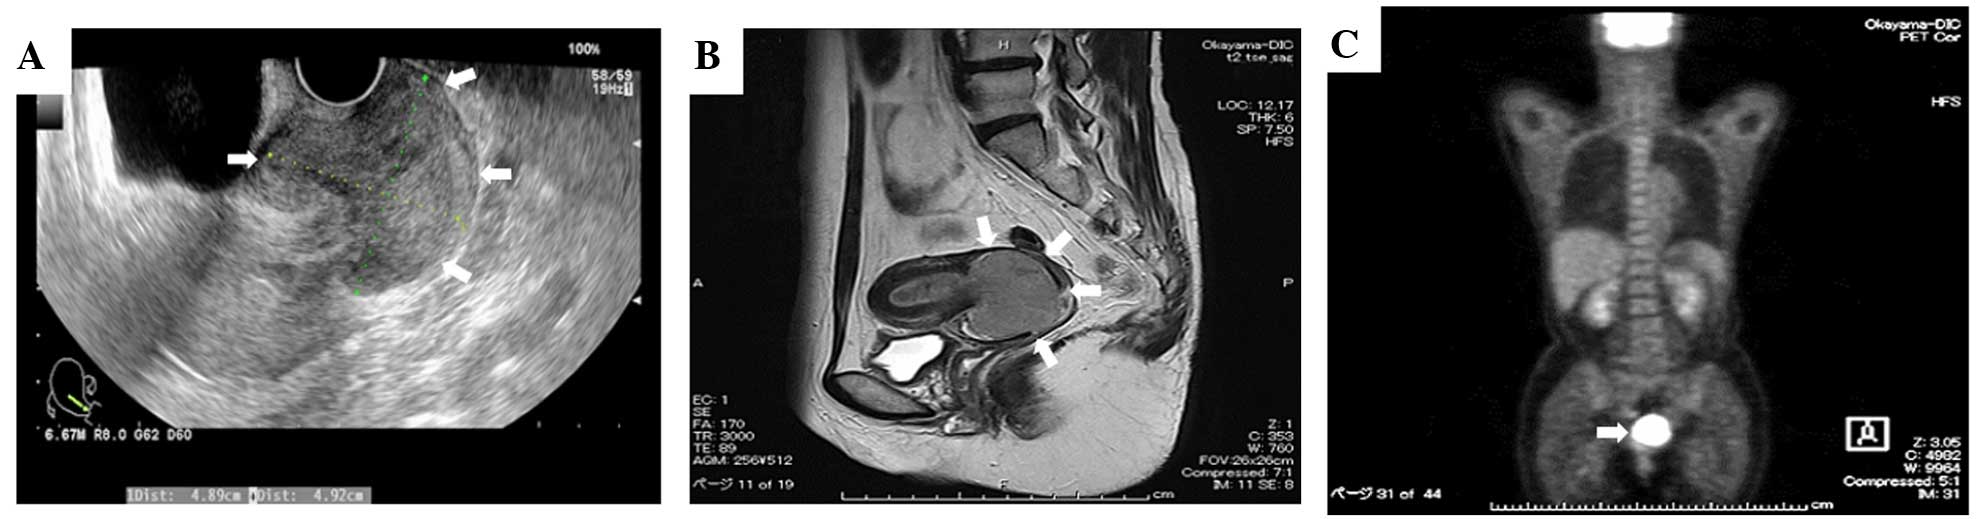

The patient was referred to our hospital and, after undergoing a detailed examination, received further treatment due to the suspicion of cervical cancer. During the first visit to our hospital, a pelvic examination revealed an enlarged cervix, while the digital examination revealed extension to the parametrium on either side of the uterus. The colposcopic examination revealed that the invasive carcinoma was a large polypoid mass in the cervical canal. The cytological diagnosis of the cervical lesion was a high-grade squamous intraepithelial lesion and the pathological diagnosis, using a punch biopsy, indicated a squamous cell carcinoma (SCC). Transvaginal ultrasonography revealed a mixed echogenic mass in the cervix, sized 49×49×57 mm (Fig. 1A). Magnetic resonance imaging (MRI) revealed a hyperintense cervical mass sized 55×51×52 mm, invading the lower uterine segment (Fig. 1B). Positron emission tomography-computed tomography (CT) revealed intense fludeoxyglucose activity correlating with a cervical and endometrial mass, without signs of metastasis to other organs or to the pelvic and paraaortic lymph nodes (Fig. 1C). The tumor marker carbohydrate antigen (CA)-125 was elevated (91.8 U/ml), but other markers, including carcinoembryonic antigen, CA19-9 and SCC antigen, were within the normal range.

Figure 1.

(A) Transvaginal ultrasonography revealed a mixed echogenic mass in the cervix. (B) Magnetic resonance imaging showed a hyperintense cervical mass invading the lower uterine segment. (C) Positron emission tomography-computed tomography revealed intense fluorodeoxyglucose activity correlating with the cervical and endometrial masses, without signs of metastasis to other organs or to the pelvic and para-aortic lymph nodes.